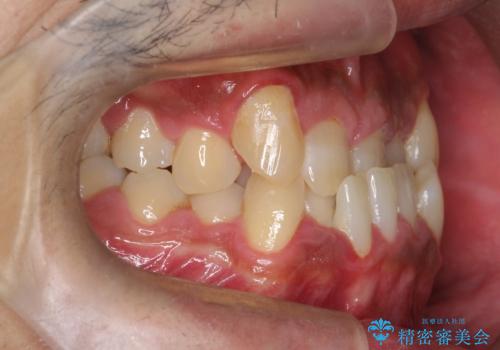

- 主訴:噛み合わせが反対になっているのを治したい

反対咬合と叢生改善のため、上下左右4番目の歯を抜歯し、審美装置にて矯正治療を行いました。